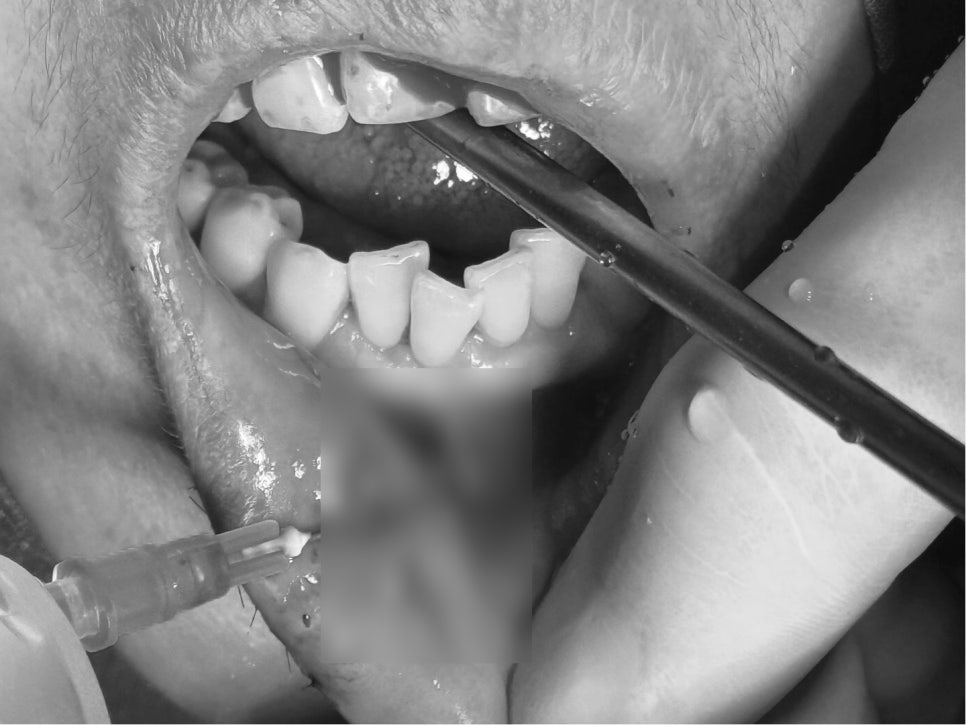

치조골 골절 및 앞니 고정장치

- 치조골 골절 & 앞니 고정술

충격으로 앞니가 뒤로 밀리거나 흔들리면,

반드시 제 위치로 되돌리고 일정 기간 고정해야 합니다.

이번 케이스에서도

부러진 잇몸뼈 제자리 정복

앞니 부목 지지대 고정 시술

이 이루어졌습니다.

이는 치아가 다시 안정적으로 뼈와 붙도록 돕는 과정입니다.

고정을 하지 않거나 늦어지면, 치아가 점점 더 움직이거나 신경이 괴사될 위험이 높습니다.